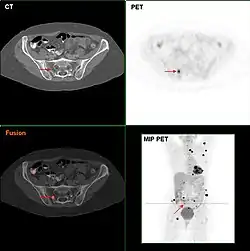

Metastatic melanomas can be detected by CT scans, MRIs, and PET/CTs, or ultrasound. PET/CT to assess for metastasis is generally recommended for people with stage IIB or greater melanoma.[11] If a person has an ulcerated lesion, or if the depth of tumor invasion is greater than 0.8 mm, then a sentinel lymph node biopsy is recommended.[11] LDH levels may sometimes be elevated in metastatic melanoma, but this is not required for the diagnosis nor staging.[11]